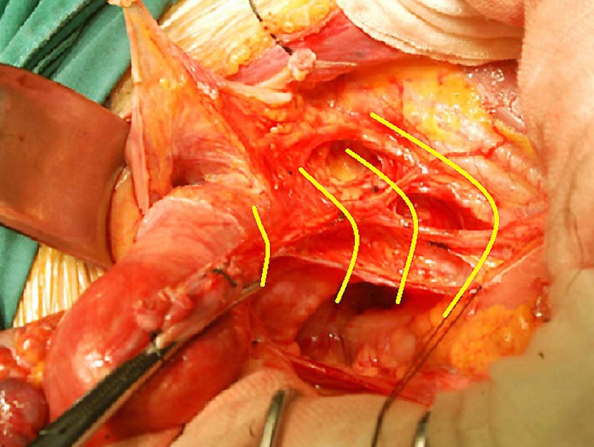

1.手术治疗 手术的优点是年轻患者可保留卵巢及阴道功能。主要用于早期子宫颈癌(ⅠA~ⅡA期)患者。①ⅠA1期:无淋巴脉管间隙浸润者行筋膜外全子宫切除术,有淋巴脉管间隙浸润者按ⅠA2期处理。②ⅠA2期:行改良广泛性子切除术及盆腔淋巴结切除术或考虑前哨淋巴结绘图活检(sentinel lymphnode mapping)。③ⅠB1期、和ⅠB2期ⅡA1期:行广泛性子宫切除术及盆腔淋巴结切除术或考虑前哨淋巴结绘图活检,必要时行腹主动脉旁淋巴取样。④部分ⅠB2期和ⅡA2期:行广泛性子宫切除术及盆腔淋巴结切除术和选择性腹主动脉旁淋巴结取样;或同期放、化疗后行全子宫切除术;也有采用新辅助化疗后行广泛性子宫切除术及盆腔淋巴结切除术和选择性腹主动脉旁淋巴结取样。未绝经、<45岁的鳞癌患者可保留卵巢。要求保留生育功能的年轻患者,ⅠA1期无淋巴脉管间隙浸润者可行子宫颈锥形切除术(至少3cm阴性切缘);ⅠA1期有淋巴脉管间隙浸润和ⅠA2期可行子宫颈锥形切除术加盆腔淋巴结切除术或考虑前哨淋巴结绘图活检,或和ⅠB1期处理相同;一般推荐ⅠB1期行广泛性子宫颈切除术及盆腔淋巴结切除术或考虑前哨淋巴结绘图活检,但若经腹或腹腔镜途径手术,手术指征也可扩展至ⅠB2期。

从左至右依次为Ⅰ、Ⅱ、Ⅲ及Ⅳ型子宫切除术的范围 Ⅰ型即筋膜外子宫切除术标本

Ⅲ型即广泛子宫切除术标本 盆腔淋巴结切除术标本